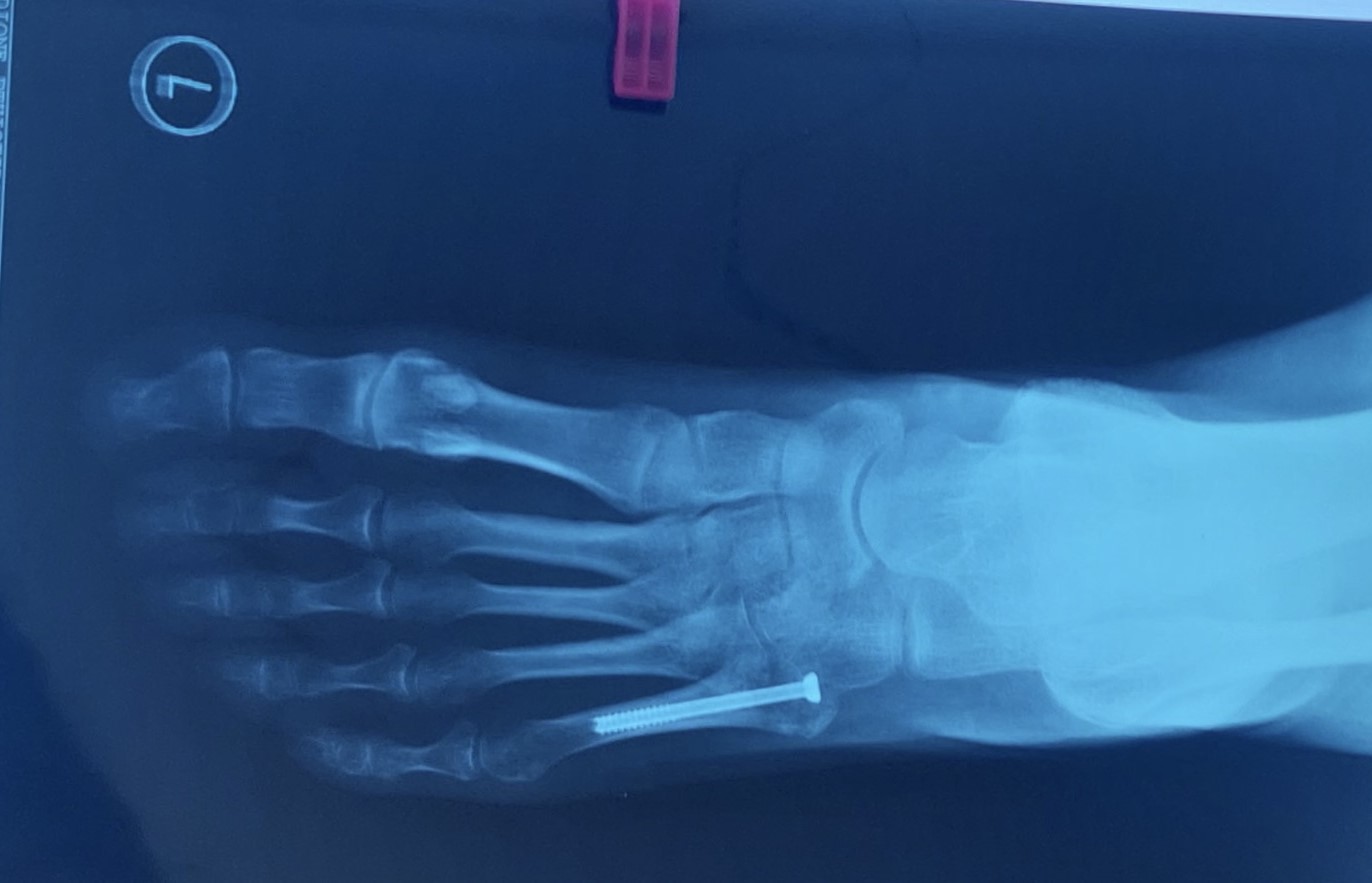

Η μέθοδος οστεοσύνθεσης ενός κατάγματος Jones συνίσταται στην τοποθέτηση ενός ενδομυελικού κοχλία, διαδερμικά. Η επάνοδος του ασθενούς στις καθημερινές και στις αθλητικές του δραστηριότητες επιτυγχάνεται στο μικρότερο χρονικό διάστημα.